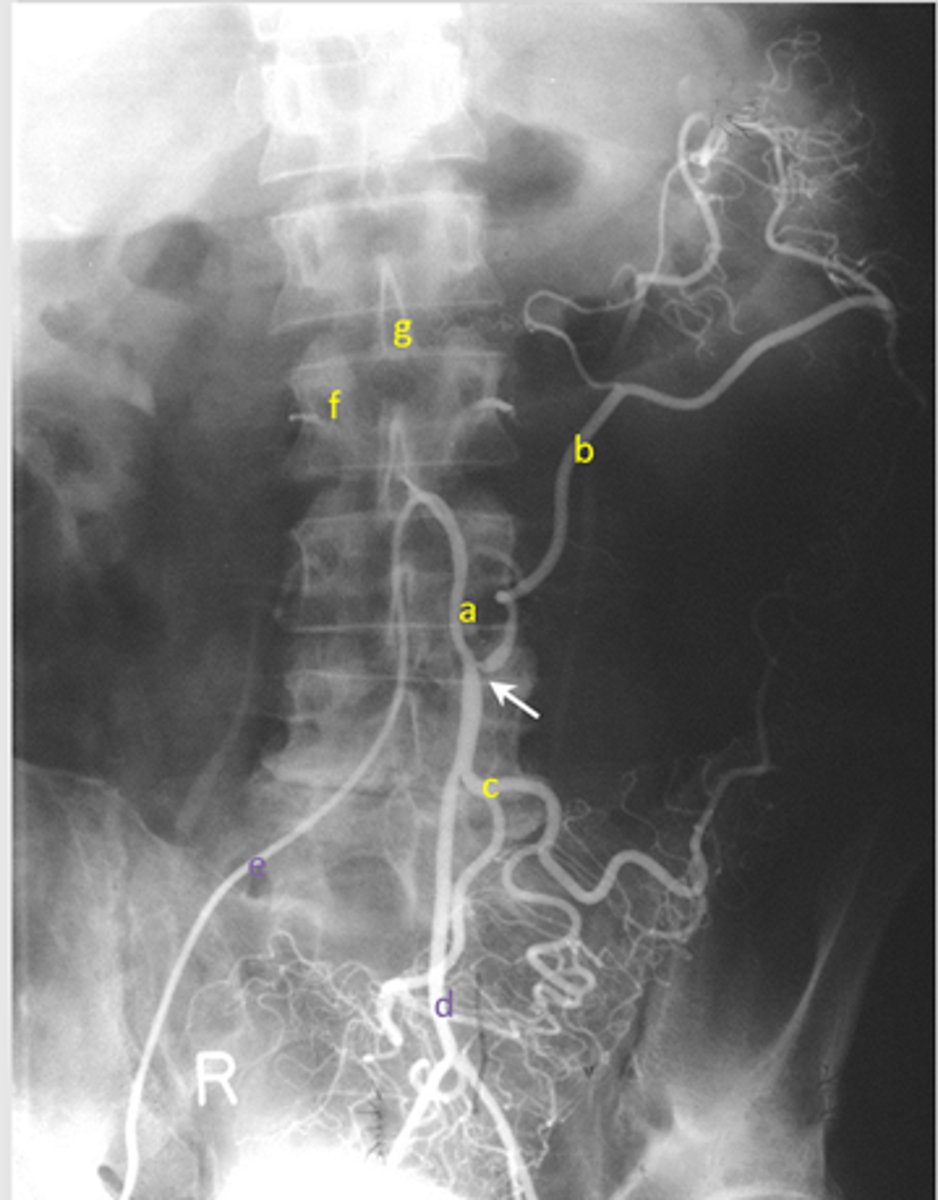

Identify pertinent anatomy of the following radiograph

knowt flashcard image

87

New cards

Identify the pertinent anatomy in the following radiograph

A: Right portal vein

B: Left portal vein

C: Portal Vein

D: Splenic Vein

E: Inferior mesenteric vein

F: Superior mesenteric vein

<p>A: Right portal vein</p><p>B: Left portal vein</p><p>C: Portal Vein</p><p>D: Splenic Vein</p><p>E: Inferior mesenteric vein</p><p>F: Superior mesenteric vein</p>